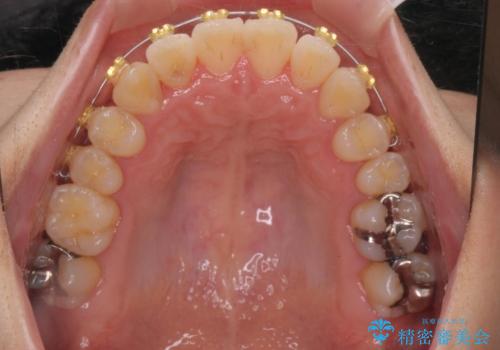

ねじれ・がたつきのある前歯を改善

- インビザライン +部分ワイヤー矯正

- がたつき・すれ違い、ねじれのある前歯の見た目、噛み合わせの改善を希望され来院されました。

4本の小臼歯抜歯を避け、下顎前歯の1本抜歯の極力少ない抜歯本数で審美的な歯並びを得る治療計画としました。

すれ違いを治すのが得意な前歯部の部分ワイヤーを用いることで、治療期間を短縮することができました。